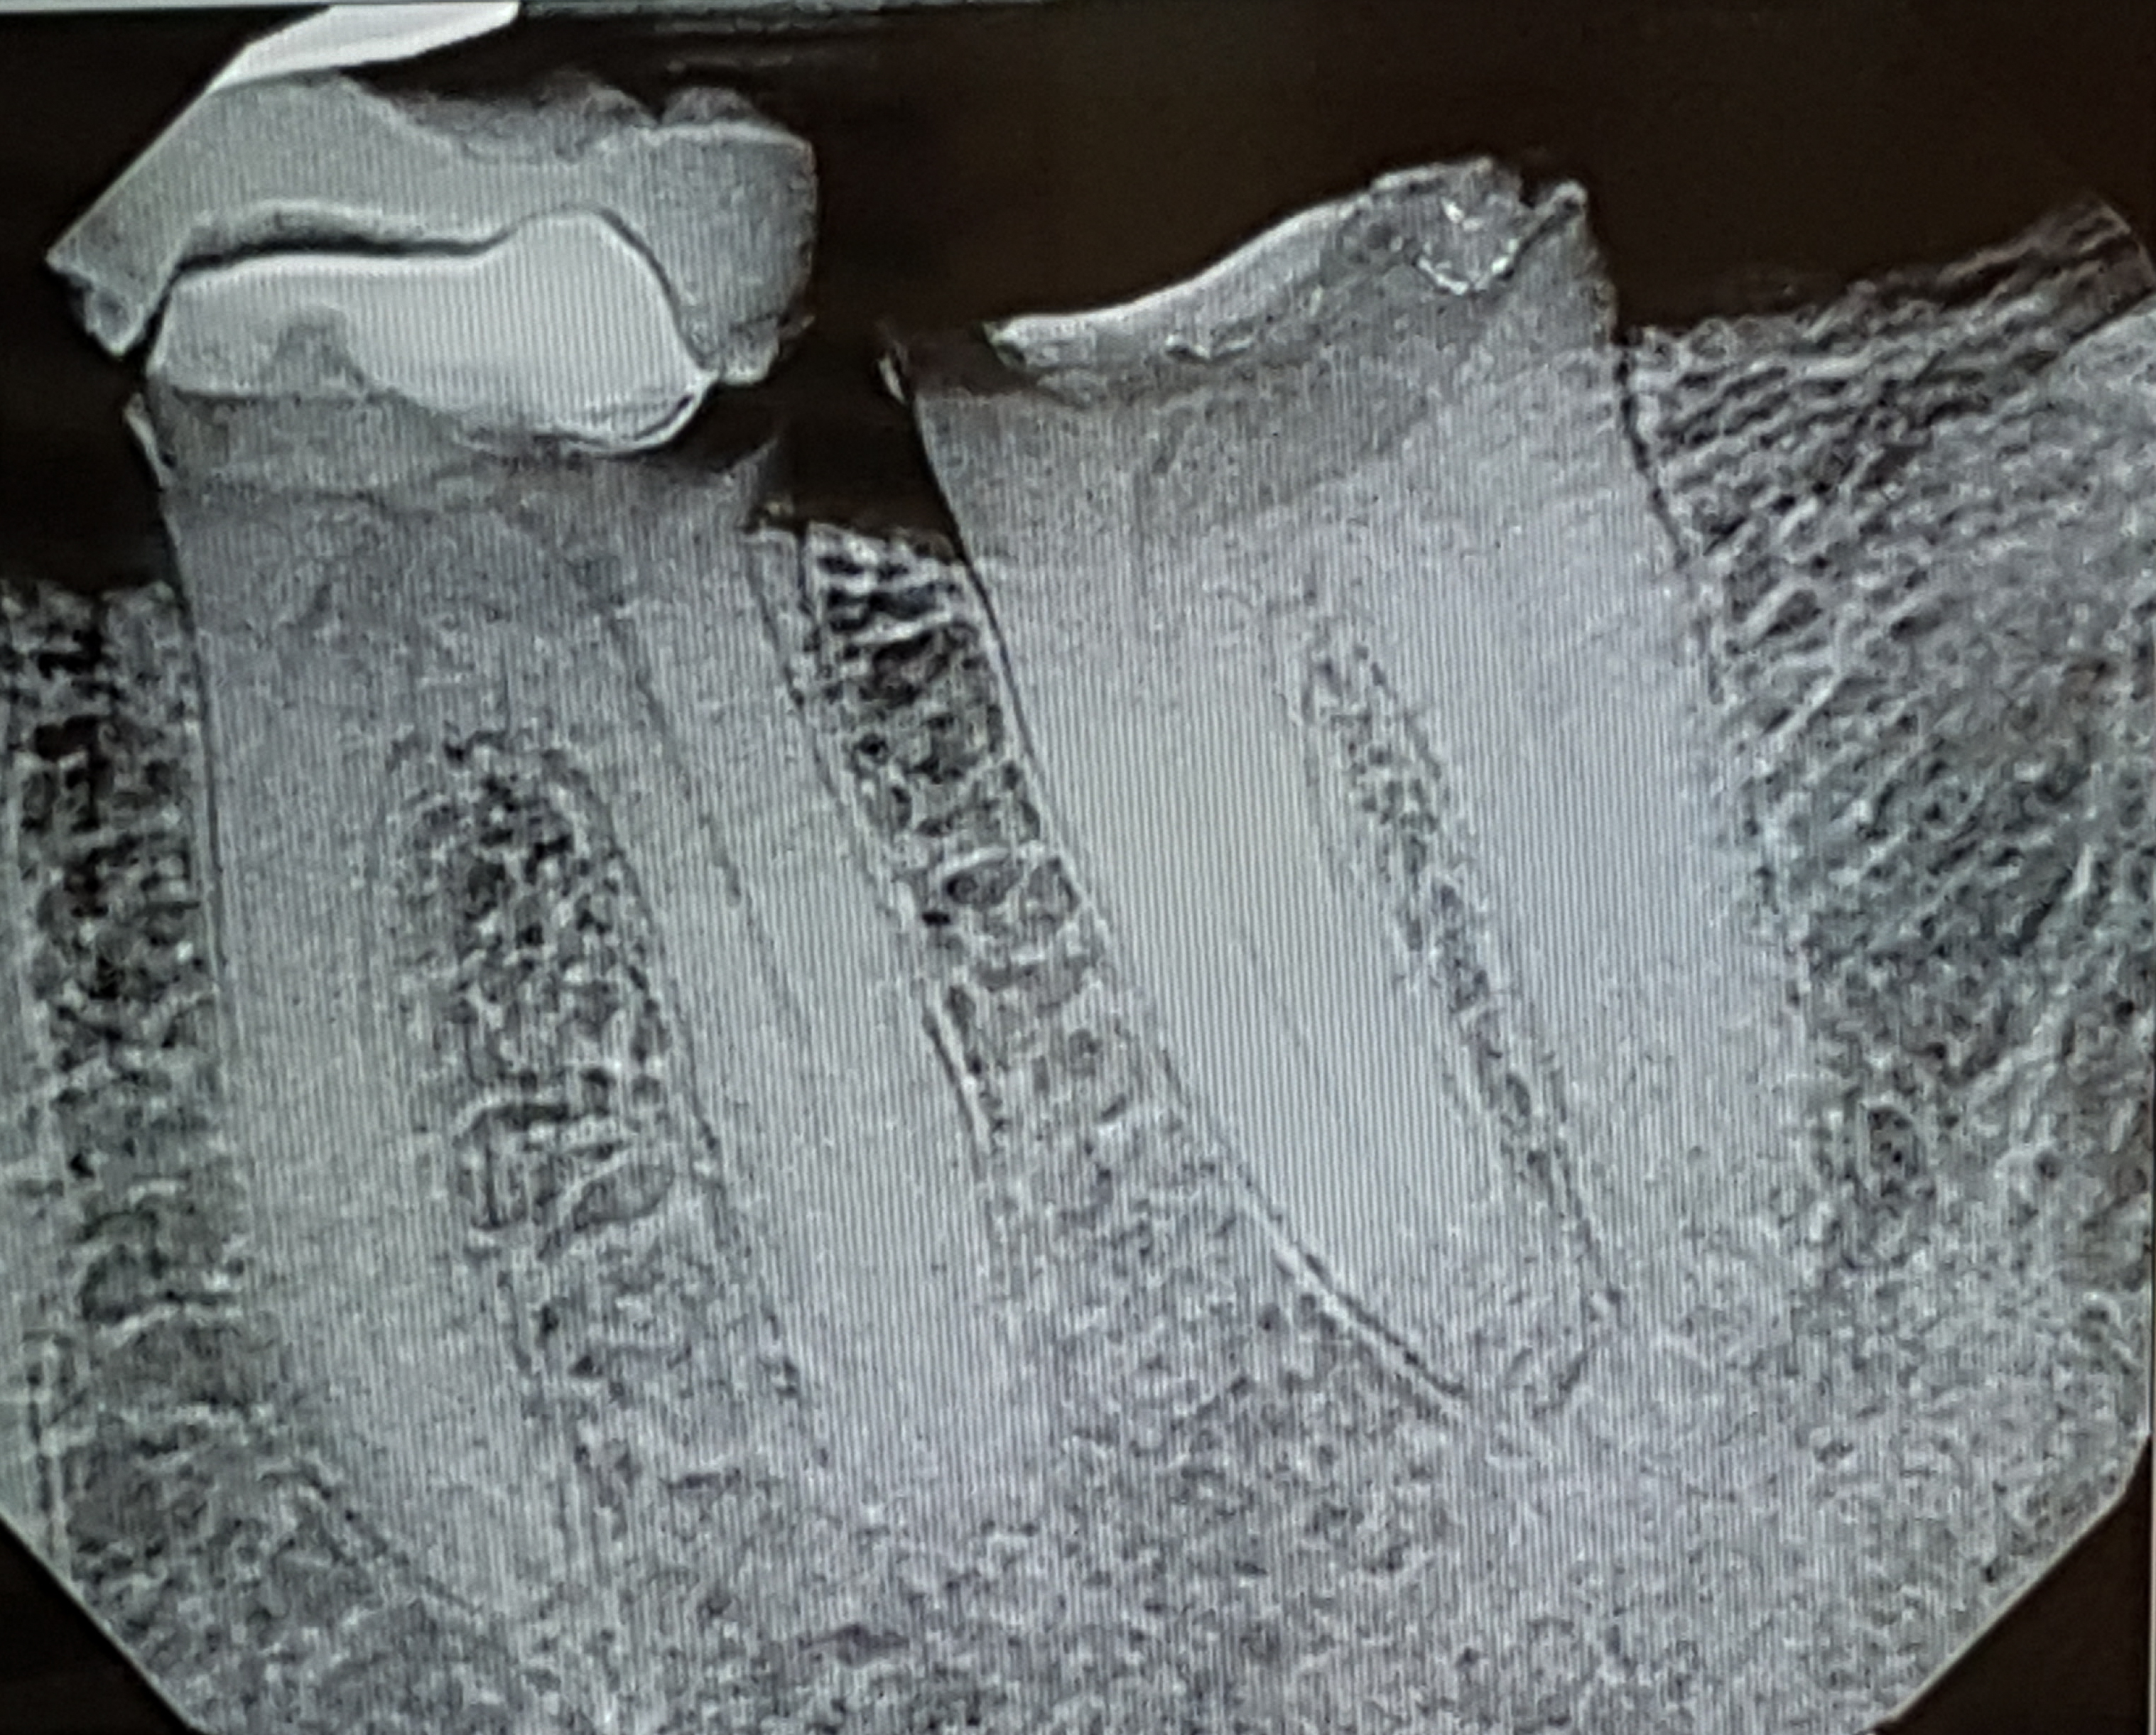

Dental Work

Ugly…